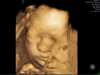

U mnie mała też zazwyczaj pozasłaniania rączkami, nóżkami i jeszcze łożyskiem, ale tyle tych USG było, że udało się akurat uchwycić chociaż kawałek buzi. Najlepsze mamy z trzecich prenatalnych, ale lekarka mocno się starała i aż cztery podejścia robiła. Bardzo jestem ciekawa jak będzie wyglądała, bo niby na tych z USG wydaje się, że podobna do mnie, ale ja jedyne podobieństwo jakie widzę to może w nosku 😀

https://zapodaj.net/plik-IC7JS1fIUp